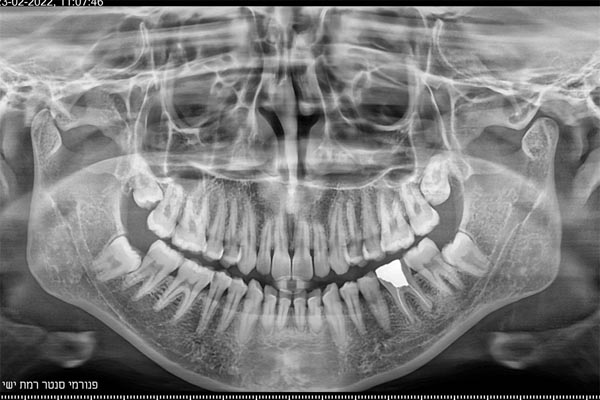

זקוקים לצילומי שיניים וחשוב לכם לקבל מענה מקצועי, אמין, מהיר ויעיל? מכון פנורמי סנטר לשירותכם! כמכון רנטגן מוביל בתחומו, אנו מבצעים צילומי שיניים ולסתות לרבות צילומי CT ואמונים על מתן שירות מקצועי, אדיב, אישי ויעיל לכל לקוח ולקוח. לנוחיותכם, אנו מספקים את מיטב שירותינו באמצעות שלושה סניפים לרבות סניף ברמת ישי, סניף ביוקנעם וסניף במגדל העמק ונשמח לעמוד גם לשירותכם לשביעות רצונכם המלאה!